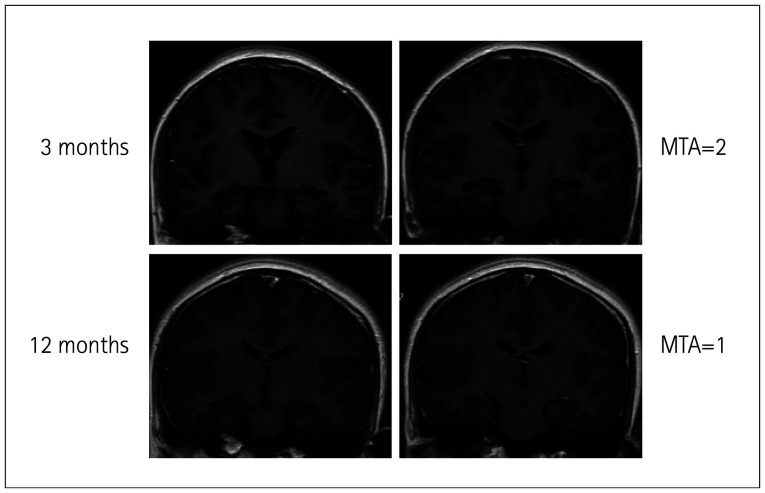

背景与目的:比较伴有和不伴有脑萎缩的抗n -甲基- d -天冬氨酸受体(anti-NMDAR)脑炎患者的临床和实验室特征。方法:对82例抗nmdar脑炎患者采用颞叶中位萎缩(MTA)和脑皮质整体萎缩(GCA)评分评价脑萎缩程度。结果:GCA(+)组癫痫持续状态发生率(pp=0.031)、脓毒症发生率(pp=0.001)高于GCA(-)组。MTA(+)组记忆问题发生率高于MTA(-)组(pp=0.002)。GCA(+)组和MTA(+)组的最大修正Rankin量表(mRS)评分(pp=0.002)和1年mRS评分(pp=0.004)均高于GCA(-)组和MTA(-)组。多元线性回归分析发现,GCA(+)组住院时间较长,治疗反应有限的病例比例较大(均pp=0.005)是发病后1年mRS评分的重要预测因素。结论:MTA和GCA可能与抗nmdar脑炎的严重程度和预后有关。

Methods: Assess cerebral atrophy using median temporal lobe atrophy (MTA) and global cortical atrophy (GCA) scores in 82 anti-NMDAR encephalitis cases.

Results: GCA (+) cases had higher proportions of status epilepticus (p<0.001), memory problems (p=0.031), sepsis (p<0.001), and mechanical ventilation need (p=0.001) than GCA (-) cases. MTA (+) cases had higher memory problems (p<0.001) and sepsis (p=0.002) than MTA (-) cases. GCA (+) and MTA (+) groups had higher max modified Rankin Scale (mRS) (p<0.001, p=0.002) and 1-year mRS (p<0.001, p=0.004) scores than GCA (-) and MTA (-) groups. GCA (+) group had a longer hospital stay and a larger proportion of cases with limited treatment response (both p<0.001) than the GCA (-) group. GCA (p=0.005) was found to be a significant predictive factor for the mRS score 1 year after onset in multiple linear regression analysis.

Conclusions: MTA and GCA may be associated with severity and prognosis in anti-NMDAR encephalitis.